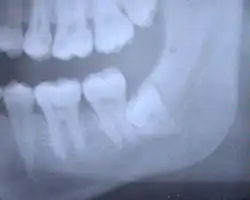

Características radiográficas

- Aumento do espaço do ligamento periodontal

- Alterações no trabeculado ósseo

- Cálculos pulpares

- Reabsorção radicular

- Alteração de continuidade da lâmina dura